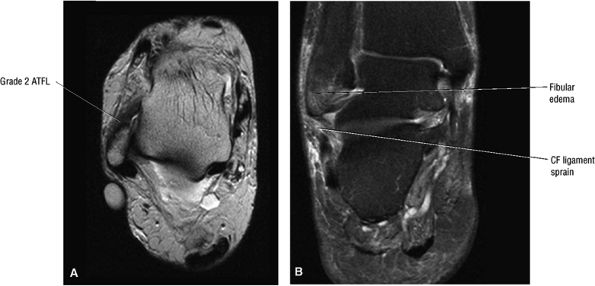

Type III: Osseous avulsion of the SPR

-

Type IV: An SPR tear posterior to the distal fibular attachment (Fig. 5.172)

![]() |

|

FIGURE 5.162 ● Peroneus brevis tendon split associated with a peroneus quartus muscle, which may contribute to mechanical crowding in the retromalleolar groove of the distal fibula. Axial PD FSE (A) and FS PD FSE (B) images.

Grade I: Stretching or partial tearing of ATFL fibers